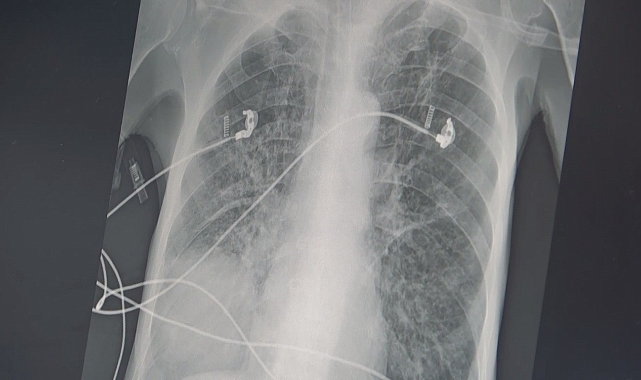

Göğüs Hastalıkları Uzm. Prof. Dr. Şevket Özkaya, "İçtiğiniz sigara 2 ölümcül hastalığın yüzde 90 sebebidir. Biri KOAH, diğeri akciğer kanseridir. Sigara içerseniz, kesecik duvarlarınızdaki elastik doku harap olur ve esneme yeteneğini kaybederek tıpkı bu naylon poşet gibi olur. 20 yıldan sigara kullanıyorsunuz bu iki hastalık ile her an yüzleşebilirsiniz" dedi.Sigara kullanımın zararlarının insanlara anlatmanın artık etkili olmadığını ifade eden Göğüs Hastalıkları Uzm. Prof. Dr. Şevket Özkaya, balon örneği üzerinde sigaranın verdiği zararı anlattı. Sigara kullanımın ortaokul yaşına kadar düştüğünü söyleyen Prof. Dr. Özkaya, "Ülkemizde 20 yaş üstündeki kişilerin en az yarısı sigara bağımlısıdır ve sigaraya başlama yaşı artık ortaokul çağlarına kadar indi. Sigaranın zararları anlatmak artık insanlarımızı etkilemiyor ama içtiğiniz sigara 2 ölümcül hastalığın yüzde 90 sebebidir. Bunlarda biri KOAH, diğeri ise akciğer kanseridir. Eğer yaşınız 40 üzeri ve içtiğiniz sigara paketi ile kullandığınız yılı çarpar, 20 paket/ yıldan daha fazla ise bu iki hastalık ile her an yüzleşebilirsiniz. KOAH teşhisi alan kişilerin büyük çoğunluğu halen sigara içen veya çok uzun süre sigara içmiş ve bırakmış kişilerdir. Hastalık sinsi ilerlediği için ve sigara bağımlıları öksürük, balgam çıkarma gibi şikayetleri önemsemedikleri için KOAH teşhisi konduğu zaman hastalar akciğer kapasitelerinin önemli bir kısmını kaybetmiş olmaktadırlar" diye konuştu."Peki sigara nasıl KOAH yapıyor"Akciğer keseciklerinin tıpkı bir balon gibi olduğuna dikkat çeken Özkaya, "Temiz havayı nefes olarak bu keseciklere aldığınızda şişer ve hava ile dolunca elastik yapısından dolayı içerdeki kirli havayı da tıpkı balonun sönmesi gibi dışarı atar. Bu mekanizma hayat kurtarıcıdır. Ancak sigara içerseniz, kesecik duvarlarınızdaki elastik doku harap olur ve esneme yeteneğini kaybederek tıpkı bu naylon poşet gibi olur ve nefes alırsınız ama balonun elastik yapısı olmadığı için kirli havayı dışarı atamazsınız ve içerde kirli hava kalır. Siz yeni bir temiz havayı nefes le almak istediğinizde keseciklerde temiz havanın gireceği yer kalmayacak ve nefes alamama yani nefes darlığı başlayacak" şeklinde konuştu."Her hücre kanserden ölecek"Kişilerin uzun yaşama imkanı da olsa her hücrenin kanserden öleceğini belirten Özkaya, "Sigaranın diğer ölümcül sebebi ise akciğer kanseridir. Biz şunu biliyoruz ki, yaşayan her sağlıklı hücrenin sonu kanser. Eğer diğer hastalıklar, kazalar ve erken ölümler olmasa ve uzun yaşama imkanı olsa her hücre kanserden ölecek. Eğer sigara kullanıyor veya kanserojen maddelere maruz kalıyorsanız, bu kansere yakalanma yaşınızı düşüren bir faktör. Örneğin; 150 veya 170 yaşında akciğer kanseri olacak bir kişi, sigara içtiği için bu yaş 100'e düşüyor. Eğer ailede kanser öyküsü varsa bu yaş daha da düşüyor. Ve 45 yaşından sonra her an kanser gelişmesi ile karşı karşıya kalınıyor. Sigara içmeye hiç başlamayarak bu iki ölümcül nefesten kurtulabilir ya da bırakarak bu iki ölümcül hastalık riskinizi azaltabilirsiniz" şeklinde konuştu. İHA